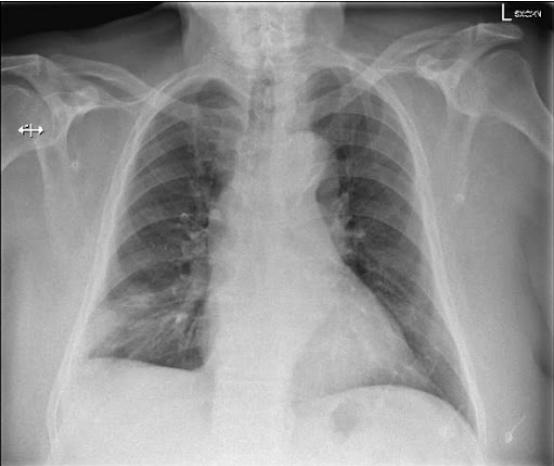

Radiografia de Tórax

- Geralmente é inespecífica, mas serve para excluir outras causas de dor torácica e dispneia.

- Achados clássicos (pouco comuns):

- Corcova de Hampton: Área em cunha sugestiva de infarto pulmonar.

- Sinal de Westermark: Oligoemia (diminuição da trama vascular) em uma área do pulmão.

- Sinal de Fleischner: Dilatação do tronco da artéria pulmonar.